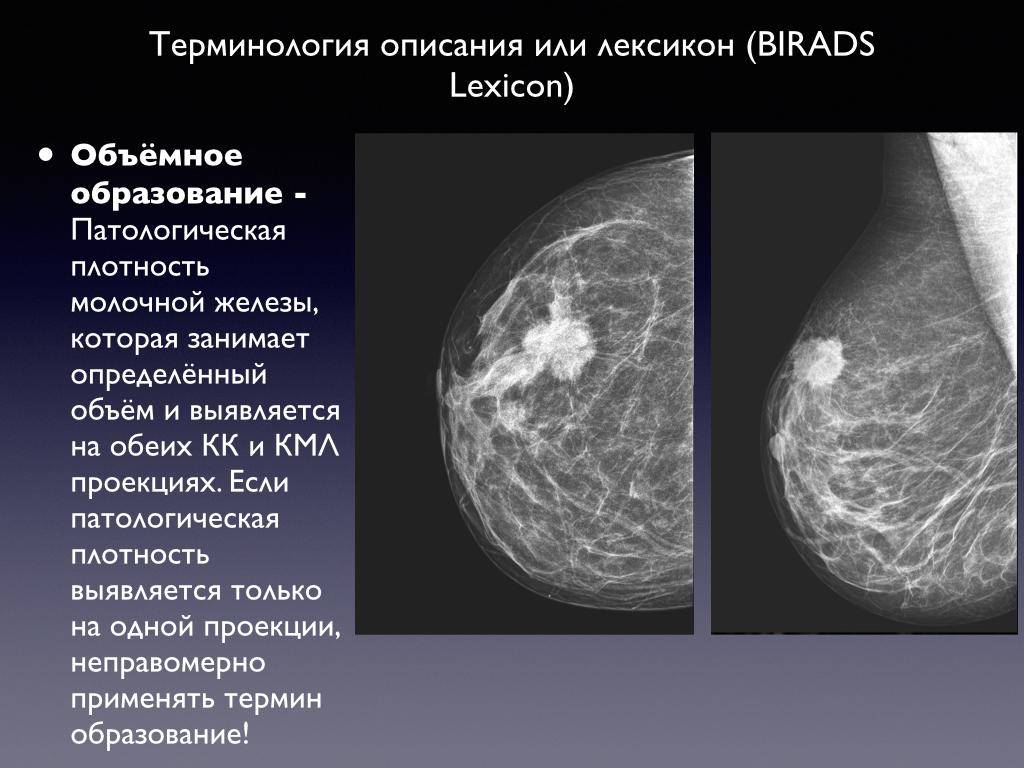

Гепатомегалия. Симптомы гепатомегалии. Умеренное увеличение печени. Умеренная гепатомегалия. Маммография косая проекция укладка. Маммография молочных желез. Маммография это исследование. Рентгеновская маммография.

Маммография косая проекция укладка. Маммография молочных желез. Маммография это исследование. Рентгеновская маммография. Подчелюстная слюнная железа на рентгене. Сиалография слюнных желез. Рентгенография слюнных желез. Контрастная сиалография слюнных желез.

Опухоль печени доброкачественная кт. Первичные злокачественные опухоли печени. Злокачественные новообразования печени кт. Первичные и Метастатические опухоли печени. Маммография. Маммограмма молочных желез. Маммография после 40 лет проводится.

Маммография. Маммограмма молочных желез. Маммография после 40 лет проводится. Виды роста злокачественных опухолей. Рост злокачественных новообразований. Злокачественные опухоли характеризуются. Форма злокачественной опухоли.

Метастатическое поражение печени. Метастатические опухоли печени. Злокачественные образования печени. Молочная железа маммография. Мастопатия на маммографии. Опухоль молочной железы маммограмма. Рик молочной железы маммографич.

Молочная железа маммография. Мастопатия на маммографии. Опухоль молочной железы маммограмма. Рик молочной железы маммографич. Опухоль головного мозга симптомы. Новообразование в головном мозге. Раковые заболевания головного мозга. Объемное образование головного мозга.

Терминальная стадия онкологии. Опухоль грудной стенки кт. Опухоль в терминальной стадии. Маммография молочных желез объемное образование. Опухоль молочной железы. Онкология молочной железы. Опухольмолочныйжелезы.

Маммография молочных желез объемное образование. Опухоль молочной железы. Онкология молочной железы. Опухольмолочныйжелезы. Доброкачественная злокачественная опухоль головного мозга мрт. Глиома головного мозга мрт. Опухоль головного мозга на кт.